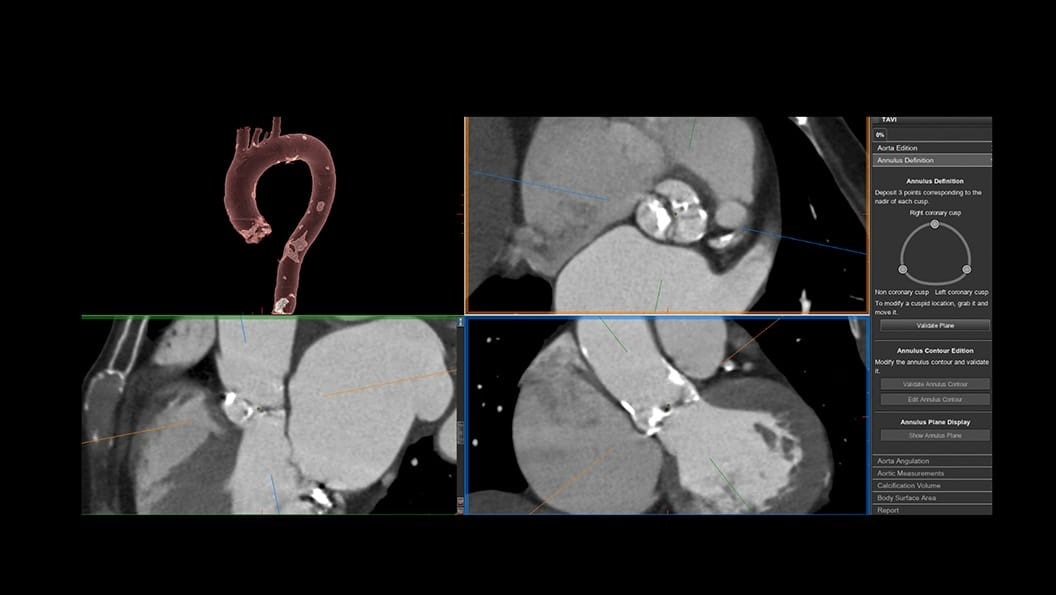

CT-Guided Interventional Care

Since becoming an important step in the patient care pathway and heart care guidelines, CT images are an invaluable tool in the cath lab, guiding procedures for precise personalized care.